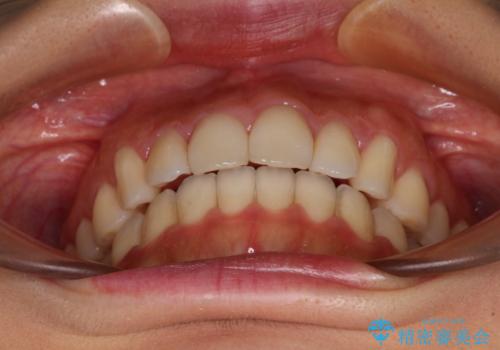

- 飛び出した前歯と口元の突出感を気にして来院された患者様です。

奥歯の咬み合わせを見ると、上顎が下顎に対して相対的に前方にありました。

口元の突出感を改善するためには、上顎臼歯を後方に移動させた咬み合わせにする必要があります。

インビザライン単体で改善することも可能ですが、達成する可能性が高くないため、カリエールディスタライザーという補助装置を併用して、より確実性を上げることとしました。

奥歯の咬み合わせを改善しながら、並行してインビザラインで歯列を整えることとしました。